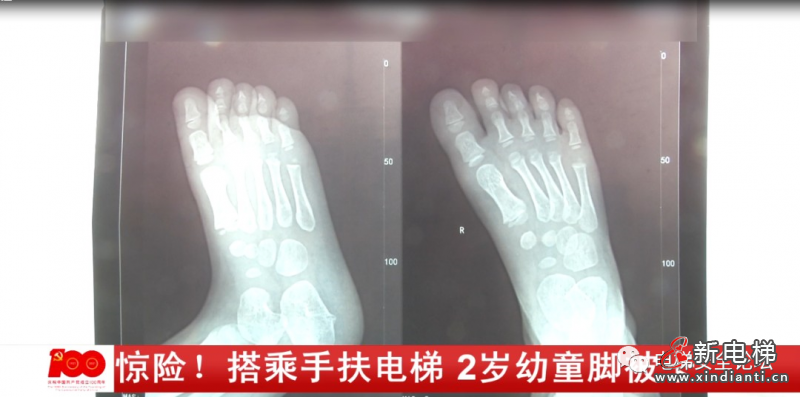

奶奶介紹,當時情況十分危急,孩子的右腳被卡進電梯的縫隙里,孩子不停的在哭喊,工作人員將孩子的腳解救出來時,腳已經(jīng)被卡得變形。小西的奶奶:那只腳小腳趾還好一點,其他的腳趾尤其是大腳趾都被卡得白白的扁扁的,我以為我小孩的腳殘廢了,沒用了。事后,小西被緊急送往附近的醫(yī)院進行治療,幸運的是孩子受傷的腳并沒有骨折。